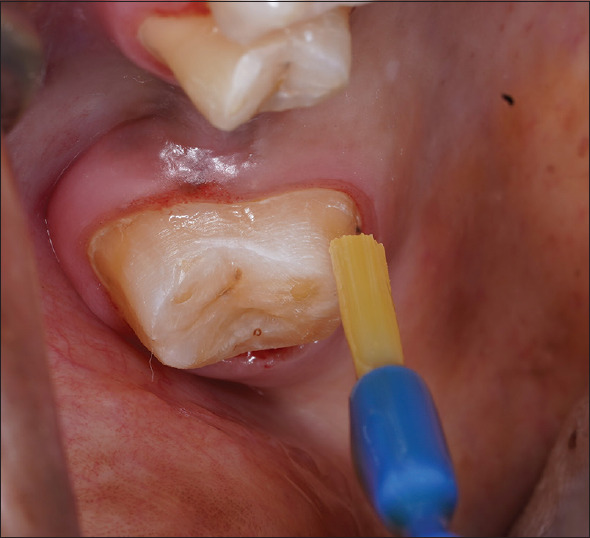

Materials and methods: 39 participants of age 25-30 years requiring vital tooth preparation were divided into Group A as control, distilled water as placebo; Group B test control, 7th generation dentin bonding agent; and Group C test, bioactive glass. Dentin hypersensitivity was evaluated on the day of preparation (T0), 7th day after preparation (T1), and 15th day (T2) at the final cementation procedure using the Schiff scale.